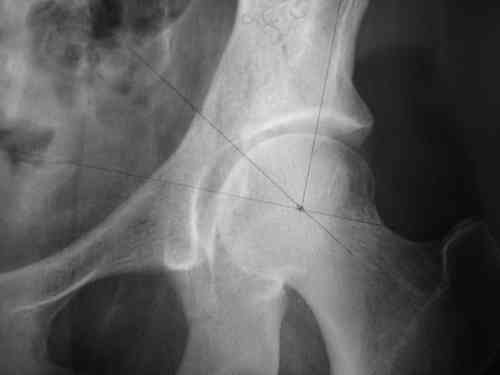

Спасибо за клинические примеры и комментарии. Если честно то просто восхищен представлеными R-ммами (классно сделали!!!). По поводу обсуждаемого больного: конечно КТ и дополнительные R-ммы сделаем. Но хочу напомнить, что после травмы прошло более 6 лет, на сегодняшний день клинически еще и R-ки признаки нестабильности эндопротеза( как бедренного компонента так и чашки). Хочется определиться как делать в аппарате или одномоментно открыто. Лично я склоняюсь к аппаратному лечению на первом этапе.

прилагаю пример с такой же давностью травмы, репонировали аппаратом

> в аппарате или одномоментно открыто. Лично я склоняюсь к аппаратному лечению на первом этапе.

задача непростая, если мало опыта в этом деле, подумайте еще раз